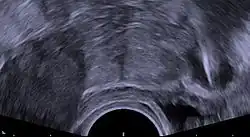

Regardless of the IUD type, some potential side effects are similar for all IUDs. Some of these side effects include bleeding pattern changes, expulsion, and pelvic inflammatory disease (especially in the first 21 days after insertion). The occurrence of IUD migration is rare, with reported rates in medical literature varying between 0.1% and 0.9%. However, when migration occurs, it can lead to serious complications such as uterine perforation and, in rare cases, bladder perforation. Bladder perforation, while uncommon (affecting only 2% of displaced IUDs), can result in symptoms like urinary frequency, hematuria, and stone formation, often necessitating surgical intervention for removal.[82] Regular monitoring and imaging, such as ultrasound or CT scans, are recommended to detect such complications early and ensure timely treatment. A small probability of pregnancy remains after IUD insertion, and when it occurs, there is a greater risk of ectopic pregnancy.[83]